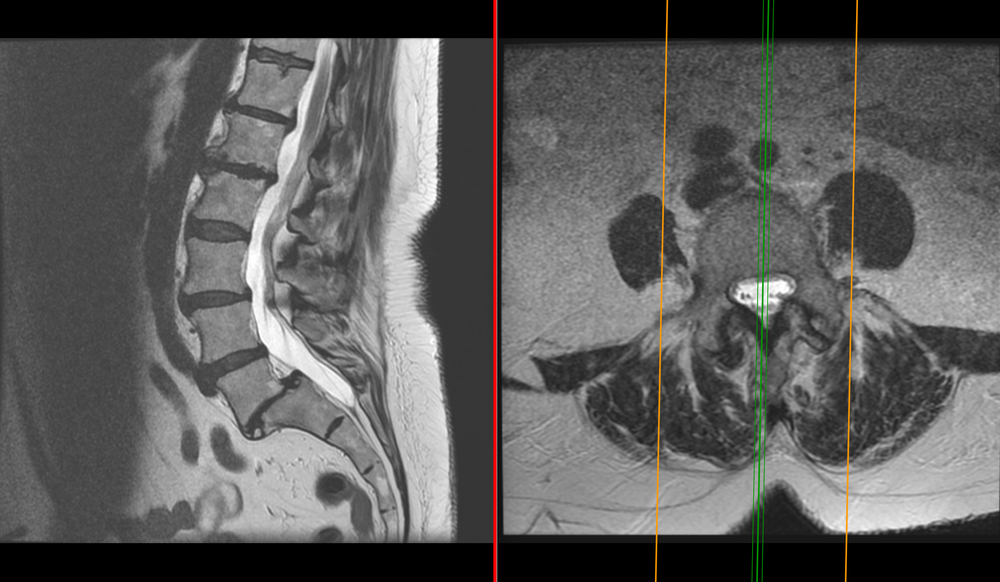

The appropriate treatment for an annular tear depends largely on the cause and severity of the damaged disc. This image illustrates a typical disc bulge that is broad-based and usually does not cause nerve compression. Annular tears Small disruptions to the outer fibrous ring of the intervertebral disc known as the the annulus fibrous can occur and these are called annular tears.

Diagnostic image testing such as magnetic resonance imaging MRI andor a computed tomography scan CT will show a bulging disc where it is located and how severe it is. From there you can be referred to a specialist who will work with you to choose your course of treatment. Treatment for C5-C6 Disc Bulging.

Herniated discs may take the form of protrusion or extrusion based on the shape of the displaced or herniated material. The following diagram illustrates this well.